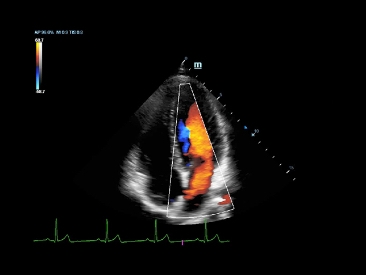

Glazing Flow

It’s a breakthrough and brand new way to demonstrate the color Doppler flow innovatively in a 3D visualization. Glazing Flow is able to provide intuitive and easy visualization of blood flow structures, especially very tiny vessels. It’s helpful for boundary definition of crossing vessels too.